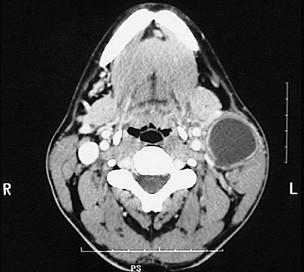

图示是鳃裂囊肿患者的CT?检查结果,关于此病的描述错误的是()A.无自觉症状B.大小不定,生长缓慢C.可继发感染D.触之有搏动感E.可形成瘘

问题 图示是鳃裂囊肿患者的CT?检查结果,关于此病的描述错误的是()

选项 A.无自觉症状 B.大小不定,生长缓慢 C.可继发感染 D.触之有搏动感 E.可形成瘘

答案 D